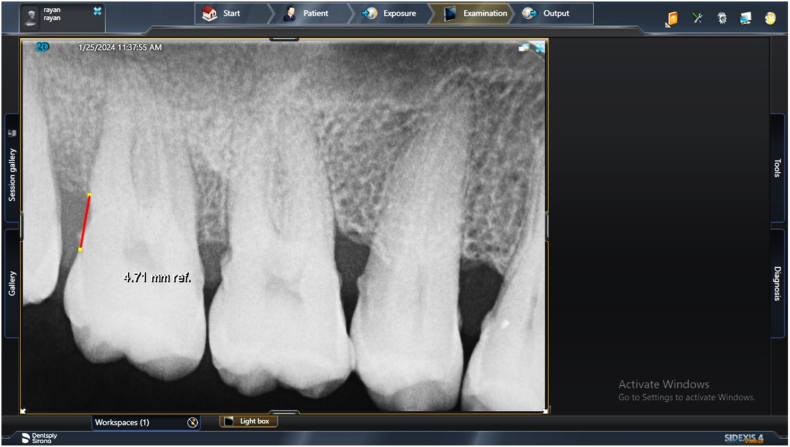

Abstract Image